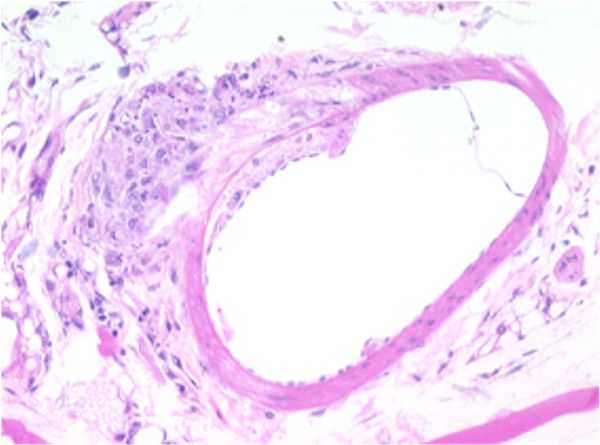

Small Artery

SMALL ARTERY: F18-01

Atherosclerotic plaque, tunica intima/media, thoracic aorta.

A focally-extensive area of the tunica media is moderately to markedly compressed by an accumulation of eosinophilic, lipoid, or fatty material within both the tunica intima and tunica adventitia.

The tunica adventitia also contains a focal, nodular, well-demarcated area of infiltrating cells characterized by mild numbers of macrophages, occasional lymphocytes, and increased collagen fibers.

The rest of the artery appears to be within normal limits. This area of constriction and corresponding proliferation may represent an area of early plaque formation.